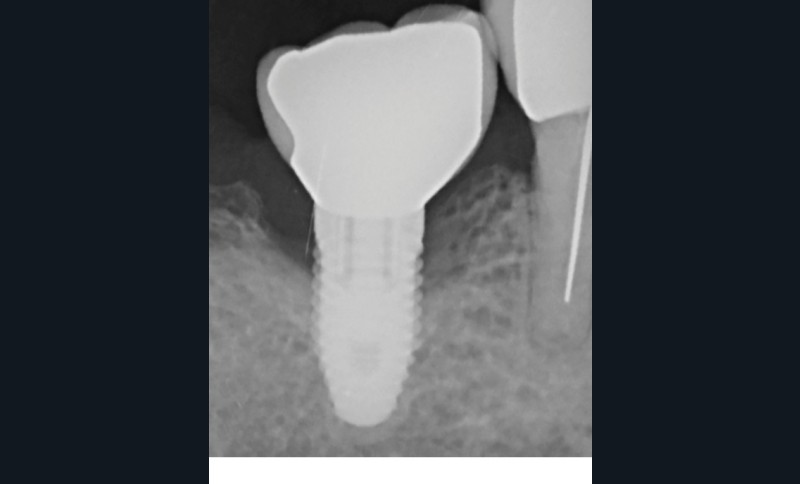

L’implant

- Péri-implantite sur l’implant 47, diagnostiquée en août 2022

- Poches de 6 à 7 mm

- Implant posé en 2017

- Nobel Replace Select RP (4,1 x 10 mm)